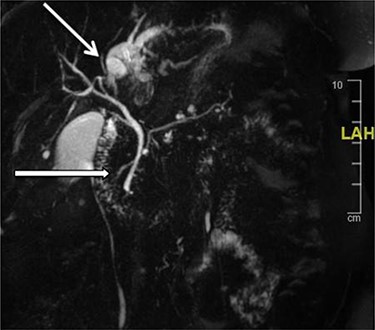

Further examination led to a diagnosis of DCBD with a separate left intra- and extrahepatic bile duct with ectopic drainage into the stomach. Magnetic resonance cholangiopancreatography (MRCP) revealed marked left intrahepatic duct (IHD) dilatation. The left IHDs were draining via an aberrant extra-hepatic bile duct into the pre-pyloric region. The left and right hepatic ducts did not communicate. It also demonstrated pancreatic divisum and multiple side branch intra-ductal papillary mucinous neoplasms (IPMN) (Fig. 3). Endoscopic retrograde cholangiopancreatography (ERCP) confirmed the MRCP findings but also revealed an intraluminal-filling defect in the left IHD (Figs 4 and 5).

MRCP: open arrow—the left IHDs drain via an aberrant (left) extra-hepatic bile duct into the pyloric region without communication with the (right) intra- and extra-hepatic bile ducts. Closed arrow—pancreatic divisum and side branch IPMN.